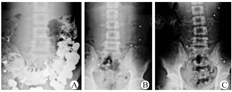

术后病理学检查诊断为肠神经元发育不良症(intestinal neuronal dysplasia,IND)14例;节细胞减少症11例。肠神经系统病理变化见表2。肠神经丛及神经节细胞病变通过免疫组化染色可见神经丛中节细胞减少、节细胞变性、神经丛中神经纤维增生及黏膜下出现孤立神经元等(图3)。

确定肠神经元病变的诊断标准为:单位神经丛中节细胞减少或增多,出现巨大神经丛、丛外孤立节细胞;神经丛中节细胞变性、固缩、变小;出现外源性神经纤维[4,5,6]。本研究中有40%(10/25)的病例标本行免疫组织化学检查(S-100染色),以显示肠神经元病变形态,进一步辅助病理诊断。